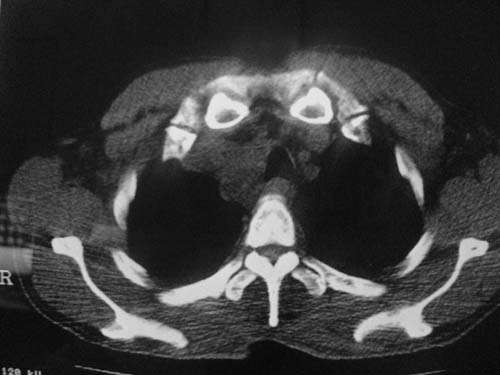

以下是引用科室第一人在2010-3-25 20:30:00的发言:[br]1:纵膈肿瘤性病变,恶性胸腺瘤可能性大伴纵膈右肺门淋巴结转移,右侧胸腔积液。[br]2:右侧肺门肿瘤性病变,纵膈淋巴结转移,右侧胸腔积液。右下叶转移。

以下是引用子期在2010-3-25 21:00:00的发言:[br]先考虑右中央型肺癌伴转移。

以下是引用江广1996在2010-3-25 22:49:00的发言:[br]通常肺癌向纵隔转移多见,纵隔肿瘤向肺内转移少见(有的表现为向肺内侵润)。本例以一元论考虑:右中心型肺癌并纵隔淋巴等多处转移。[br][br][本贴已被 江广1996 于 2010-3-25 22:50:07 修改过]

以下是引用yangyudong333在2010-3-26 6:43:00的发言:[br]“冰冻纵膈”,考虑纵膈淋巴瘤伴肺内及胸膜侵润。